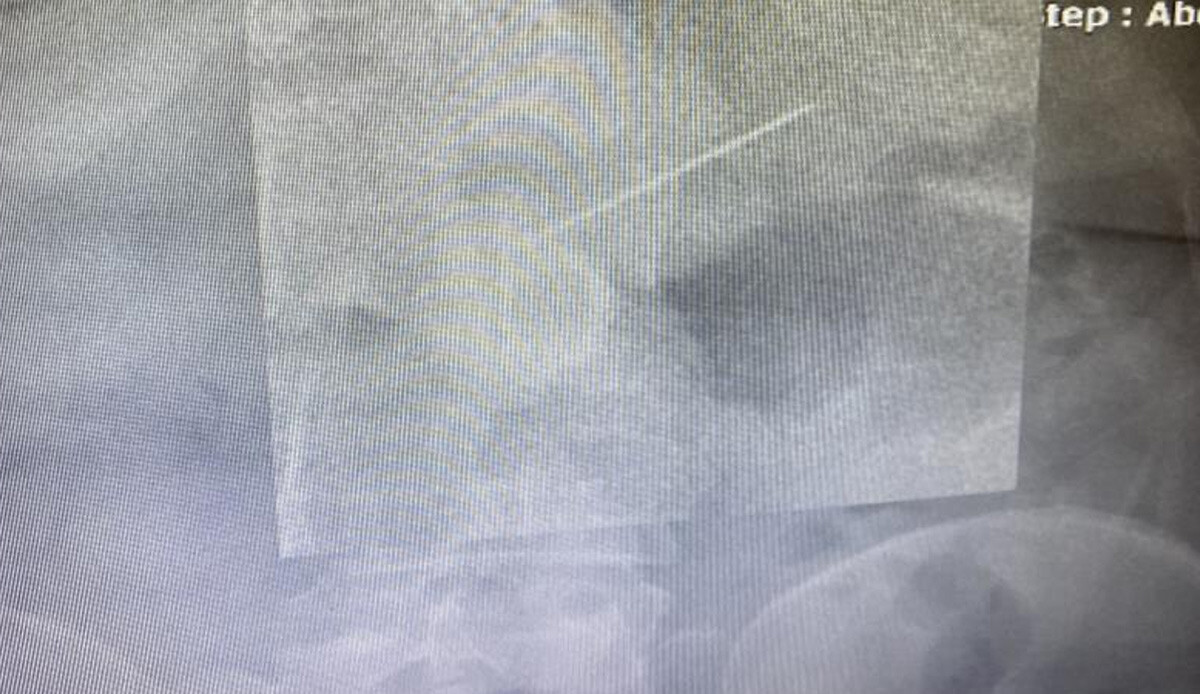

Başörtüsünü takmak isterken ağzında tuttuğu iğne boğazına kaçtı. Gaziosmanpaşa’da yaşayan 2 çocuk annesi 45 yaşındaki Semiha Keçeci, iddiaya göre 23 Ocak'ta acelesi olduğu için başörtüsünü düzeltirken ağzına aldığı iğneyi hapşırınca yuttu. Yaklaşık 3,5 santimlik iğneyi yuttuğunu anlayan kadın şok olurken bir anda acı içinde kaldı. Başakşehir Çam ve Sakura Şehir Hastanesi acil servisinde tedavi altına alınan kadına hemen film çekildi. Toplu iğnenin mideye ulaştığı belirlenirken gerçekleştirilen endoskopik işlemle hastanın midesindeki iğne olduğu noktadan alındı. Keçeci, rahat bir nefes alırken, Başakşehir Çam ve Sakura Şehir Hastanesi Genel Cerrahi Bölümü’nden Op. Dr. İsmail Çalıkoğlu, gerçekleştirilen tedaviye ilişkin bilgi verdi. Mideye ulaşan iğne filmdeki görüntüsüyle gözler önüne serilirken, Op. Dr. Çalıkoğlu, özellikle çocuklarda yabancı cisim yutmalarına karşı uyardı.

"Hastamız bize geldiğinde başörtüsünü bağlamak için kullandığı iğnesini bir süre ağzına almak istediğini belirtti. Daha sonra bir hapşırma gelişmiş, aniden nefes çekme olayı olduğu için yemek borusuna bu iğne kaçmış. Bir ihtimal bu soluk borusuna da gidebilirdi böyle ani nefes almalarda o zaman soluk borusunun incelenmesi gerekirdi, akciğere kaçardı. Bu şartlarda yemek borusundan midesine doğru ilerleme olmuş. Bize başvurduğunda bu işin üzerinden 2-3 saat geçmişti, iğne yavaş yavaş ilerlemişti. Biz acil servilerde yaptığımız görüntülemelerde iğnenin henüz daha midede olduğunu, daha fazla ileriyle gitmediğini gördük. Akabinde hastamızı endoskopi ünitemize aldık, burada yaptığımız endoskopide de tam mide çıkışında mide mukozası dediğimiz en iç tabasına saplanmış şekilde gıda artıklarının arasında durduğunun gördük. Zor da olsa özel aletlerimizi kullanarak iğnemizi tuttuk, daha sonra endoskopi kanalının içinden hastamıza herhangi bir zarar vermeden dışarıya çıkarttık. Bu iğnenin hastamıza bu aşamaya kadar herhangi bir zarar vermediğini yemek borusunda, midesinde yırtılma yapmadığını gördük."